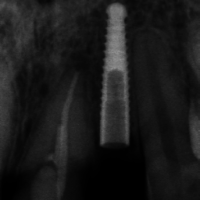

La radiografia endorale iniziale e l’esame Cone Beam mostrano che vi è una buona disponibilità ossea verticale, ma una disponibilità di osso in senso mesio-distale al limite dei protocolli per l’inserimento di un impianto Exacone da 3,3 mm di diametro (Figg. 3-6); per questo motivo decidiamo di utilizzare il nuovo impianto Leone da 2,9 mm di diametro e lunghezza di 14 mm, progettato soprattutto per le agenesie degli incisivi laterali superiori e inferiori.

- Fig. 3

- Fig. 4

- Fig. 5

- Fig. 6